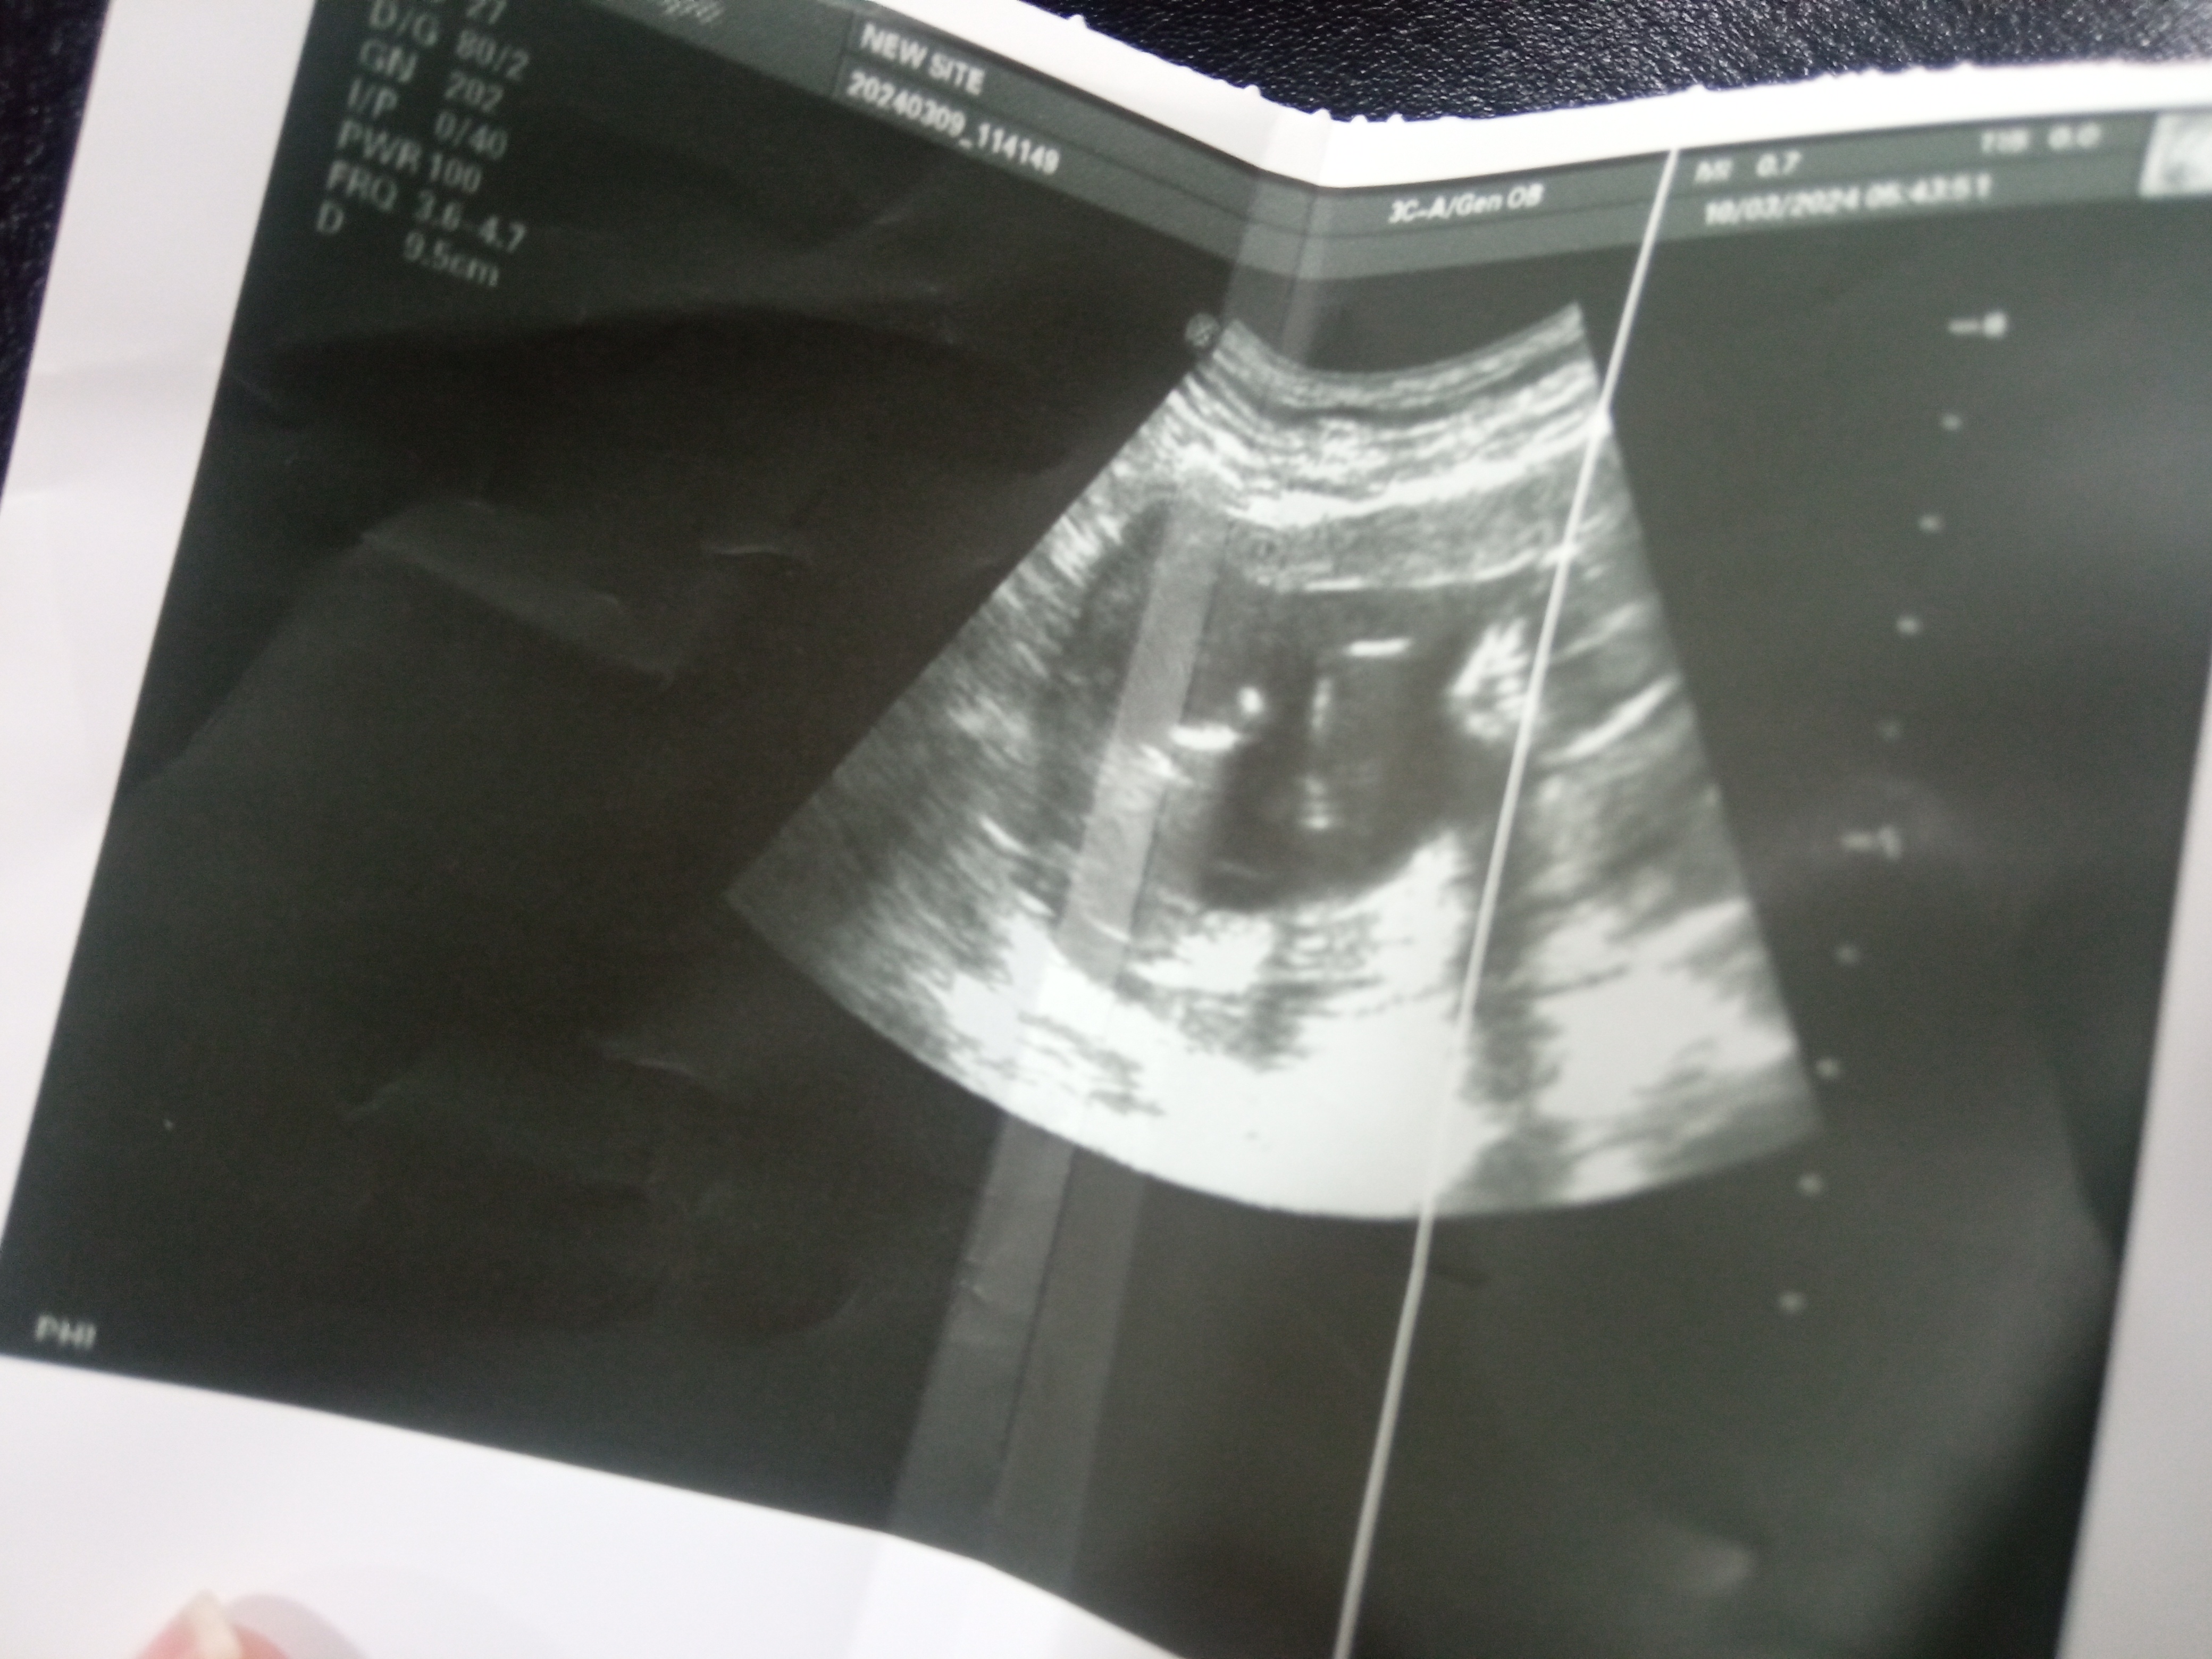

تم ارفاق صوره توضيحيه..هل واضحة لمعرفة جنس الجنين؟وما هو جنسه

دكتور انا بالشهر الرابع من حملي وهي صورة الجنين مبين جنسه بس ممكن تقوللي وتأكدلي